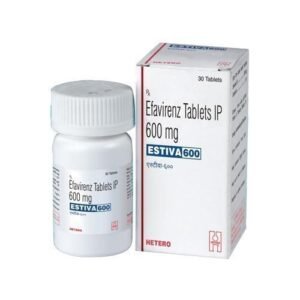

Estiva 600 mg Tablets

₹899.005 ★(1)

Estiva 600 mg Tablets

₹899.005 ★(1)₹2,088.00 -